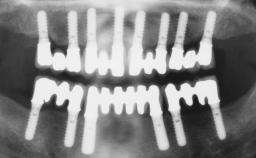

Immediate Loading of Six Implants in the Maxilla and Final Restoration with a Full-Arch Gold/Ceramic FDP Involving the Concept of Tilted Implants

# of Implants 6

Type of Implants One-Piece|Reduced-Diameter

Bone Augmentation Horizontal|Simultaneous

Surgical SAC classification

SAC Level Complex

Defining Characteristics Fully edentulous upper jaw to be rehabilitated with four or more implants

Modality Fixed hybrid bridge on 5+ implants

Bone Volume Deficient horizontally, allowing simultaneous augumentation